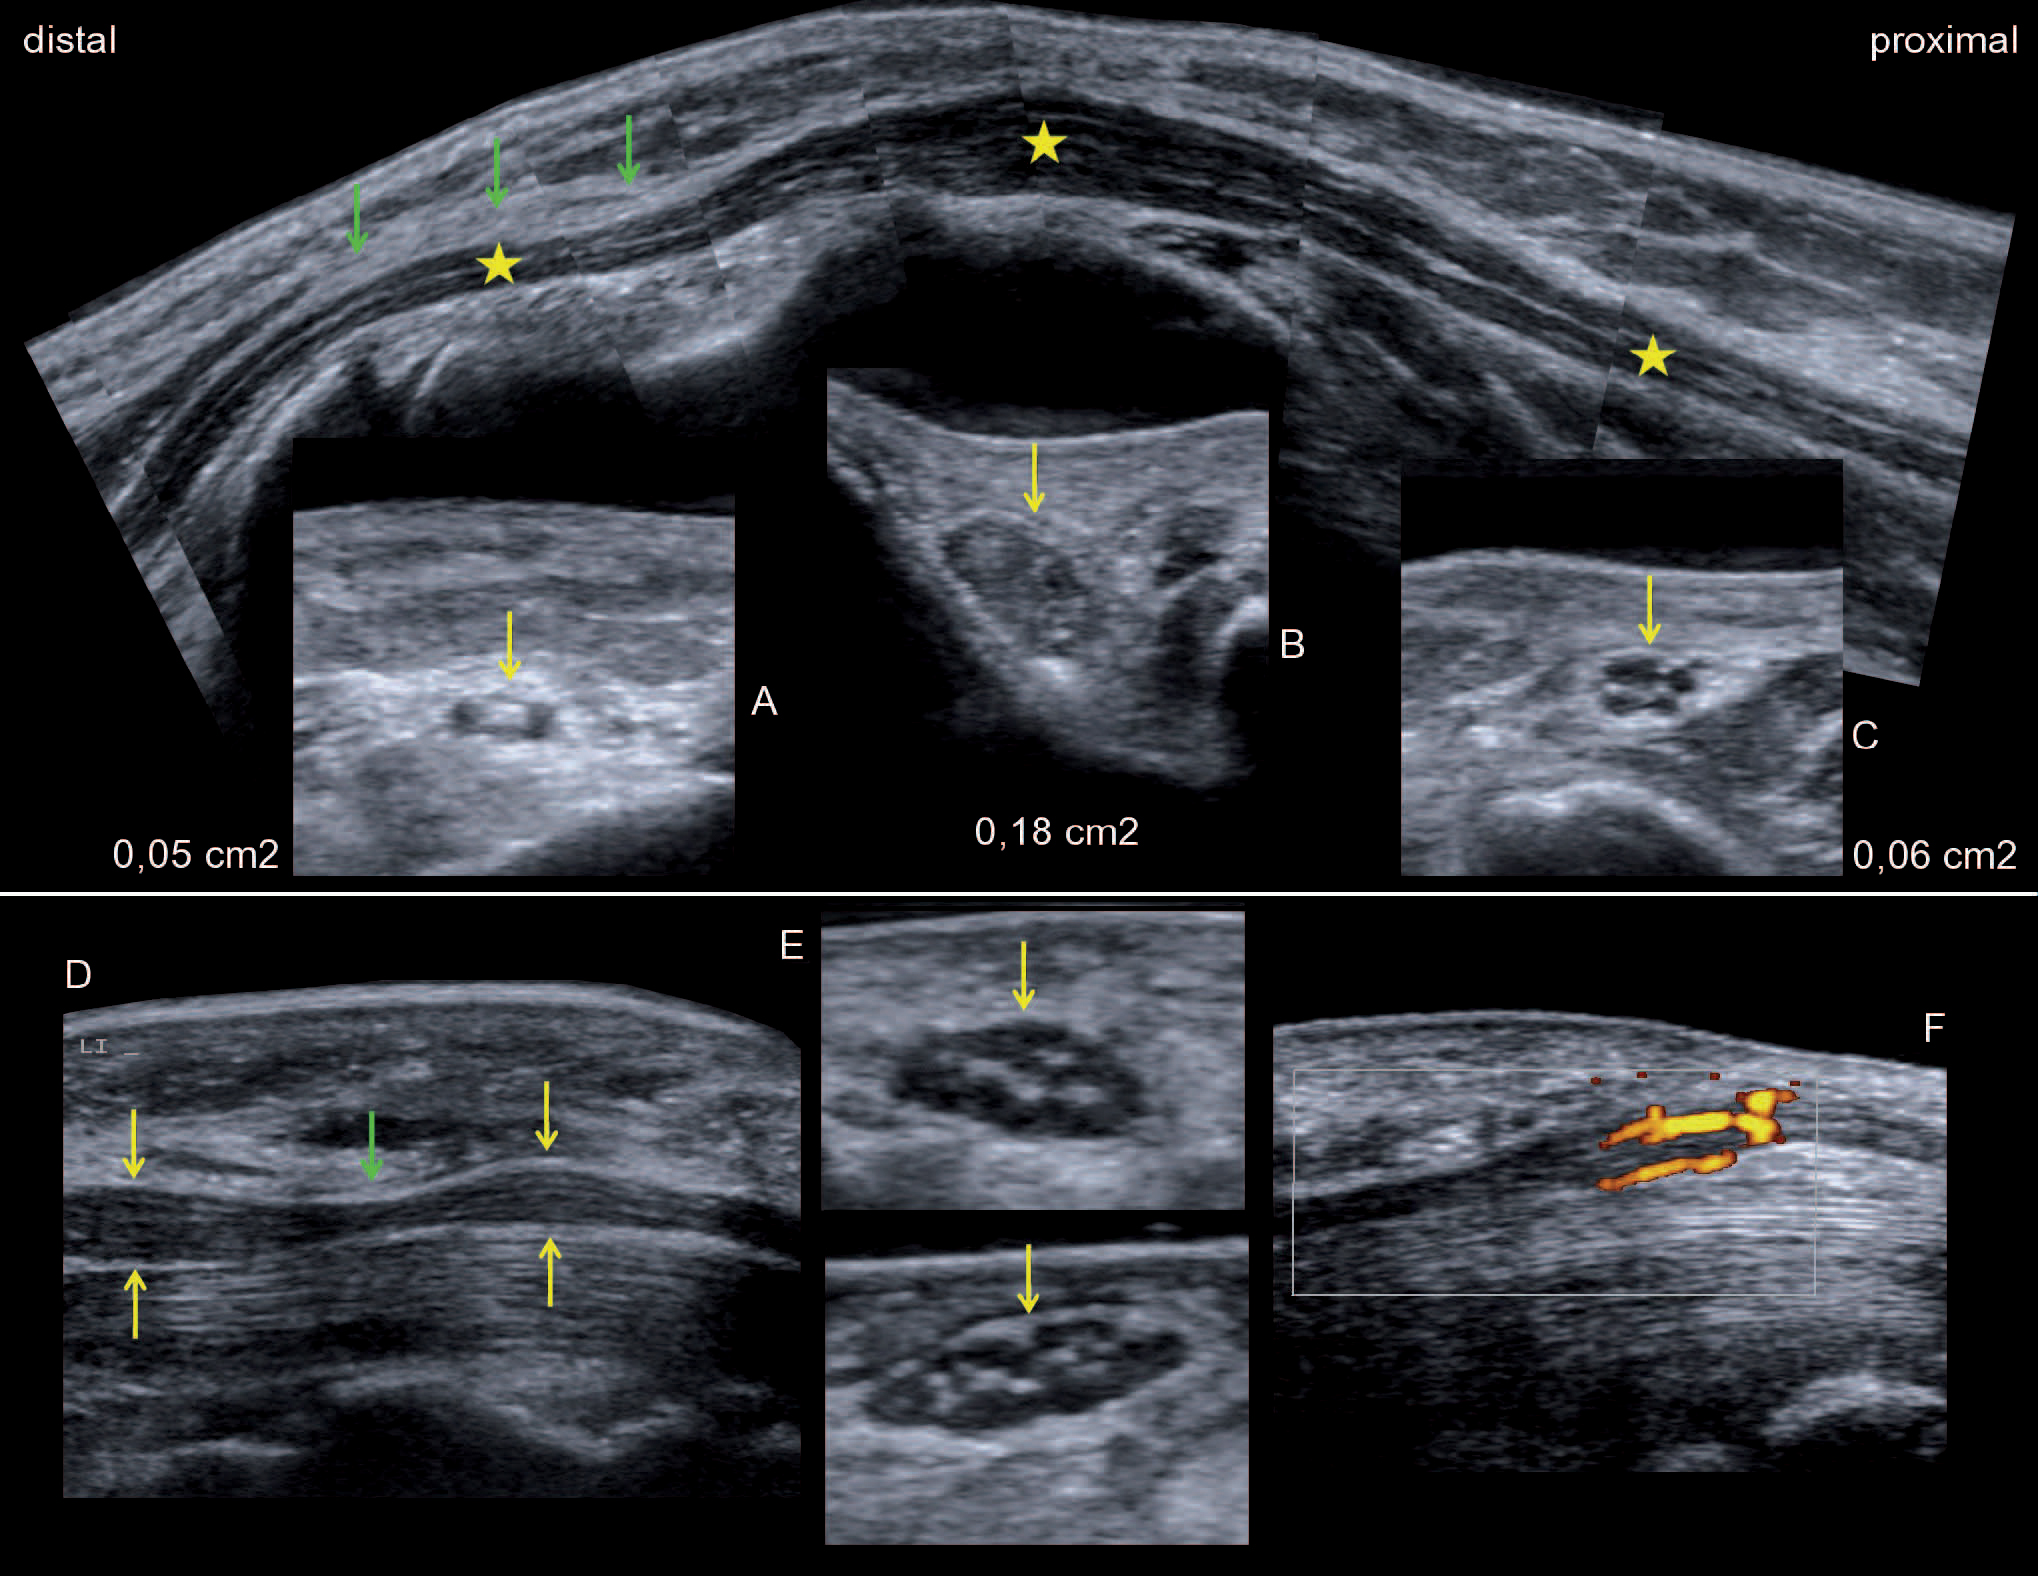

Millimetergenaue Diagnose Mit Hrus Springerlink